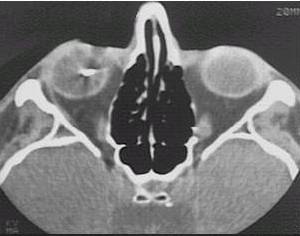

What type of image is it? CT scans or MRI scans (T1 or T2

weighted)

Which plane the image is in? axial, sagittal or coronal.

Describe the image: In ophthalmology, most of the pathology will

be focused on the globe, orbit or the brain. If it were the viva,

ask the examiner for some history.

Examine the following strucutres in order and always compare the

two sides for asymmetry(ies):

globe: eye present (enucleated eye or implant)?

lens present (aphakia)? opacities in the vitreous (blood or foreign body)?

calcification in the retina (retinoblastoma)? calcification in the optic

nerve (drusen)? any abnormal thickening of the sclera (compared with the

opposite eye, thickening suggests scleritis)?